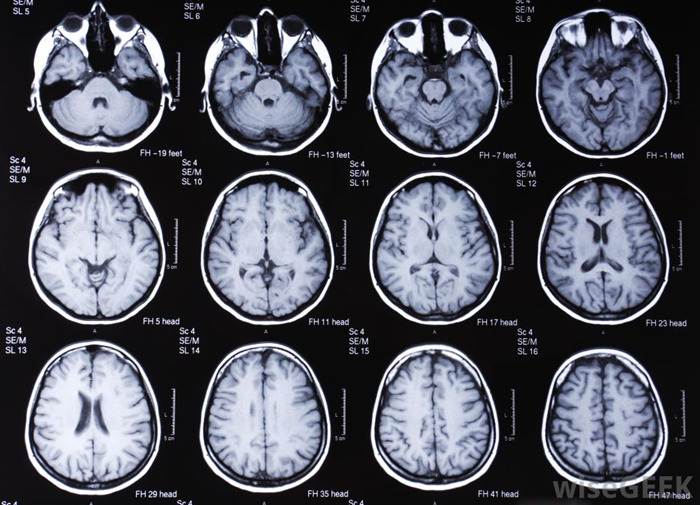

- На Эхо-ЭГ и МРТ головного мозга — невропатолог;

- результаты МРТ, компьютерной и рентгенографической томографии;